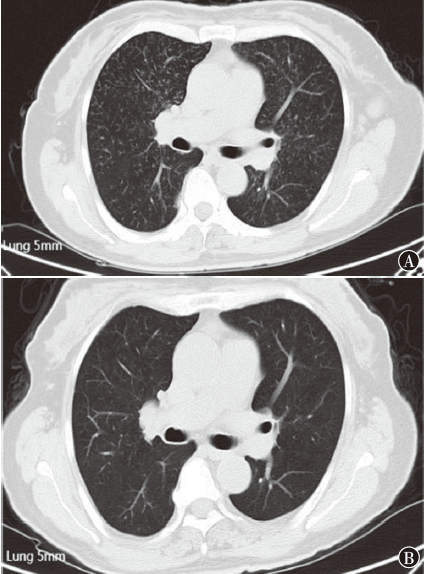

维布妥昔单抗联合吉西他滨治疗难治性Ⅳ期蕈样肉芽肿1例

蕈样肉芽肿为皮肤T细胞淋巴瘤,常累及皮肤,累及重要脏器的晚期患者预后差。维布妥昔单抗已被批准为晚期蕈样肉芽肿的一线治疗,对于维布妥昔单抗治疗后无改善的难治性蕈样肉芽肿患者,后续治疗选择有限,化疗效果有限。现报道1例应用维布妥昔单抗单药、受累野放疗及维布妥昔单抗联合吡柔比星等方案治疗效果欠佳,应用维布妥昔单抗联合吉西他滨方案后皮肤及受累脏器较前好转的Ⅳ期蕈样肉芽肿病例,以期为该类患者的治疗提供帮助。